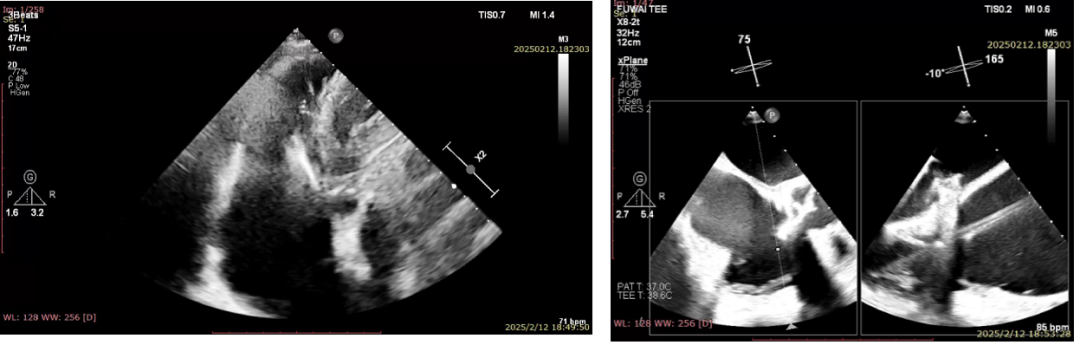

术前超声

术前超声可见三尖瓣瀑布样返流